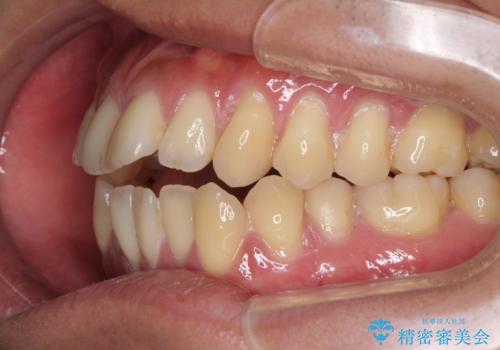

- 上下前歯の隙間と口元の出っ張った感じを気にして来院された患者様です。

上下の隙間は舌突出癖によるもので、またその癖により前歯が前方に出ている状態でした。

口元の出っ張りを改善するため、上下左右第一小臼歯4本を抜去し、ワイヤー装置にて矯正治療を行うこととしました。

舌の突出癖を改善するためのトレーニングを指導していましたが、なかなか改善することができず、ワイヤー装置を外してからも上下前歯に隙間ができやすい状況でした。